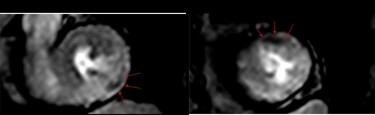

90 - 100 Schlägen pro Minute oder Tachykardien die auf Vorhofflimmern die Herzvorhöfe schlagen nicht mehr regelmäßig sondern vollführen zahlreiche Flimmerbewegungen oder Vorhofflattern. 52 männlich mit Angina pectoris eingeschlossen die wegen des Verdachts auf eine stenosie-rende KHK eine kardiale Adenosin-Stress-Perfusions-MRT inklusive Cine-Ruhe-Funktion Adenosin-Stress- und -Ruhe-Perfusion und Late gadolinium enhancement und. Kombiniert wird die Untersuchung mit einer myokardialen Vitalitätsdiagnostik Late-Enhancement zur Identifizierung infarzierter MyokardbezirkeFibroseEntzündung.

Bei der Untersuchung der Durchblutung der Herzkranzgefässe Stress MRT wird Ihnen über 4 Minuten ein Medikament verabreicht Adenosin das zu. Indikation der DobutaminAdenosin - Stress MRT.